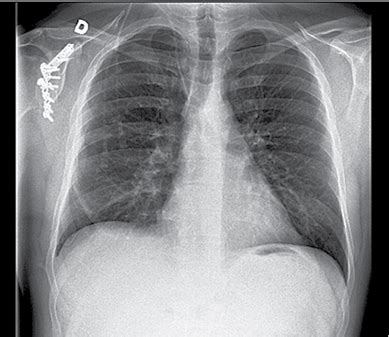

Įgytą plaučių uždegimą galima įtarti, kai atsiranda ūminiai respiraciniai simptomai: stiprus kosulys, skrepliavimas, krūtinės skausmas, dusulys, padidėjęs kvėpavimo dažnis ir karščiavimas. Diagnozę galima patvirtinti krūtinės ląstos rentgenograma - tada matomi visi uždegiminiai pakitimai plaučiuose. Kraujo tyrimas. Sergant plaučių uždegimu nustatomas padidėjęs leukocitų kiekis, aptinkama toksinių granuliocitų, padidėja eritrocitų nusėdimo greitis, taip pat C reaktyvinio baltymo (CRB) koncentracija kraujo serume.

Krūtinės ląstos rentgenograma